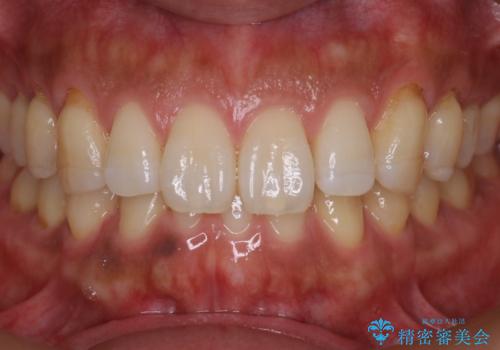

著しい八重歯が気になる インビザラインでの矯正治療